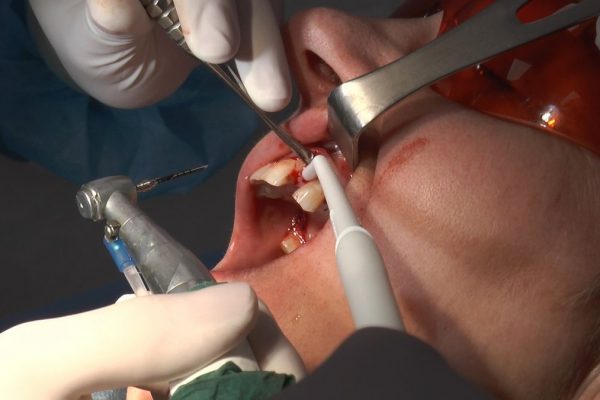

W ostatni weekend czerwca 2018 roku kursanci II Sezonu Preludium Implantologii odbyli piątą, finałową sesję, która w całości podporządkowana była praktyce. W ciągu dwóch dni zabiegowych Lekarze uczestniczący w szkoleniu przeprowadzili szereg zabiegów pod kierunkiem dr n.med. Violetty Szycik. Wszczepili 17 implantów oraz przeprowadzili ekstrakcje i zabiegi regeneracyjne kości. Zabiegi były wykonywane także w sedacji dożylnej z udziałem specjalisty anestezjologii i intensywnej terapii dr Jolanty Grzybowskiej. Preludium implantologii to nowy program edukacyjny dla adeptów implantologii stomatologicznej, którego celem jest wprowadzenie do implantologii poprzez pozyskanie wiedzy w szerokim zakresie i uwzględnieniem szczegółów mających decydujące znaczenie dla powodzenia leczenia implantologicznego. Ale tak jak wszystkie szkolenia w Instytucie Vivadental, w tym wiodące Practiculum Implantologii, zorientowane jest na praktyce i samodzielnym wykonywaniu zabiegów pod kierunkiem Mentora. To najlepsza edukacja w medycynie zabiegowej, a zarazem najlepszy start do implantologii.